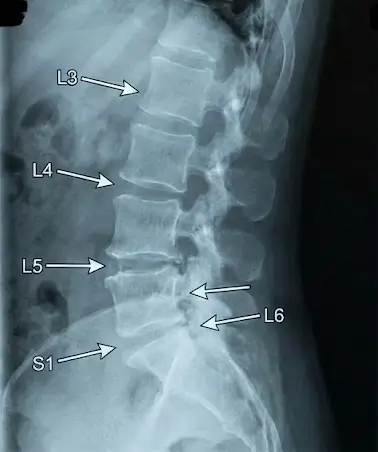

Degenerative disc disease (DDD) is a condition where intervertebral discs in the cervical spine or lumbar spine lose hydration, elasticity, and structural integrity over time. Disc deterioration can lead to reduced spinal flexibility, disc height loss, and increased stress on facet joints and spinal nerves.

DDD can cause chronic neck or back discomfort, limit spinal mobility, and increase risk of nerve compression. Early diagnosis using MRI, CT scans, and X-rays allows targeted treatment to preserve spinal function and maintain mobility.

Diagnosis of degenerative disc disease (DDD) involves evaluating cervical and lumbar spine structures using MRI, CT scans, X-rays, and neurological exams to assess disc health, nerve compression, and spinal alignment.